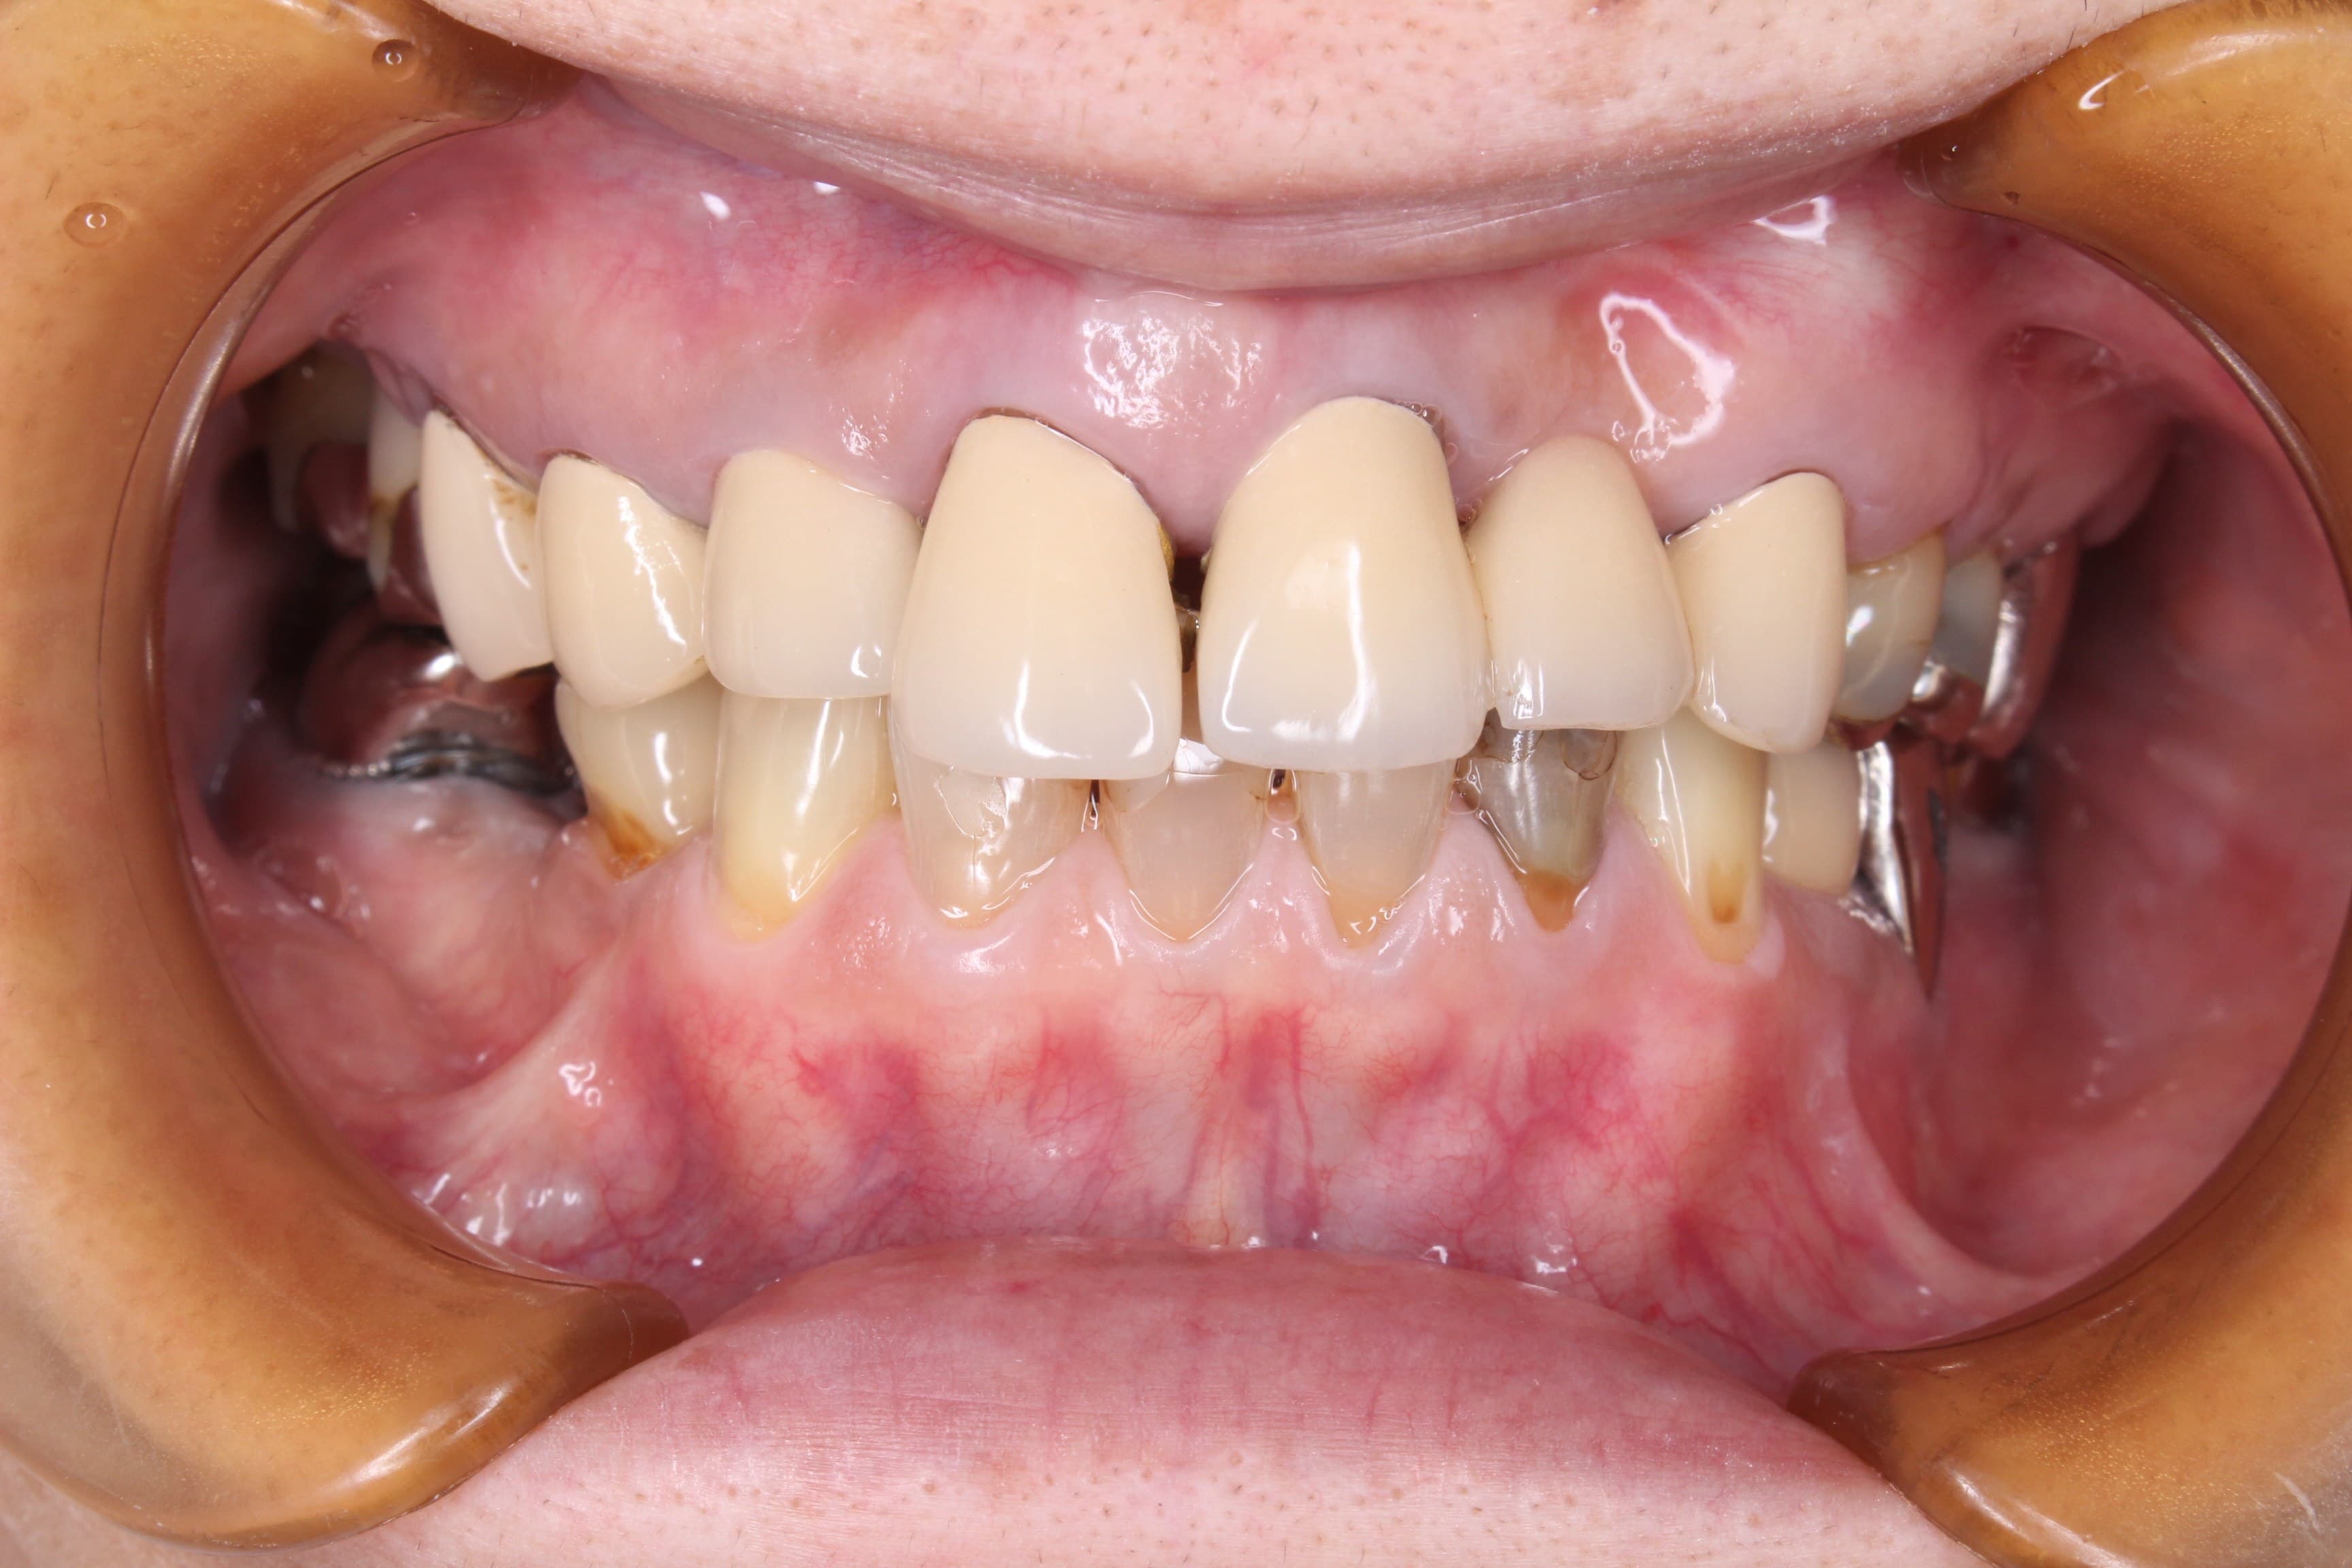

歯周病治療後です。

歯周専門治療では悪くなる可能性は徹底的に排除していきます。

現在は院長の治療途中です。